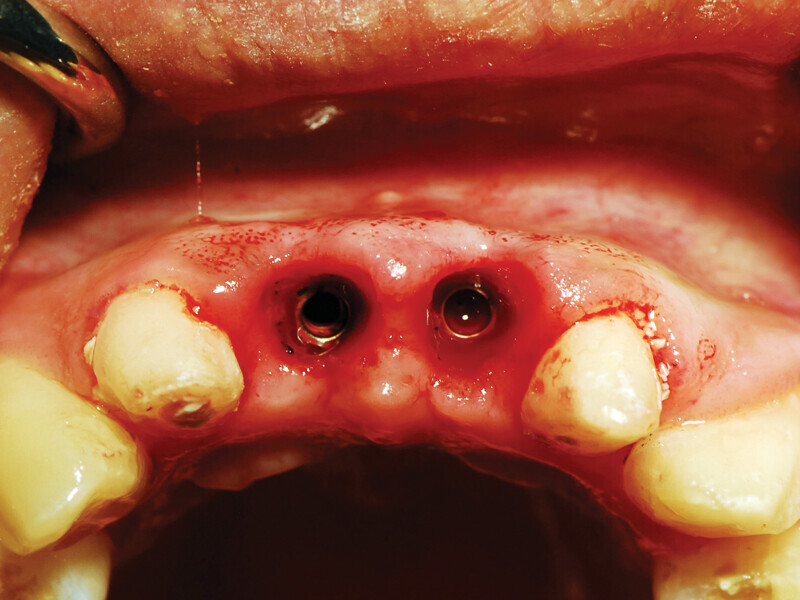

Figs. 4a: Implant to be uncovered (4a) presents with two options depending on width of attached gingiva available. Wide band of attached gingiva will remain after removal of tissue over cover screw, and the diode is utilized in a spiral pattern starting at center until fully exposed (4b). With the narrow band of attached gingiva present, an elliptical cut is made with the diode and tissue is pushed buccally and lingually to preserve the attached gingiva (4c). (Photo provided by Dr. Gregori M. Kurtzman)

Fig. 4b: Implant to be uncovered (4a) presents with two options depending on width of attached gingiva available. Wide band of attached gingiva will remain after removal of tissue over cover screw, and the diode is utilized in a spiral pattern starting at center until fully exposed (4b). With the narrow band of attached gingiva present, an elliptical cut is made with the diode and tissue is pushed buccally and lingually to preserve the attached gingiva (4c). (Photo provided by Dr. Gregori M. Kurtzman)

Fig. 4c: Implant to be uncovered (4a) presents with two options depending on width of attached gingiva available. Wide band of attached gingiva will remain after removal of tissue over cover screw, and the diode is utilized in a spiral pattern starting at center until fully exposed (4b). With the narrow band of attached gingiva present, an elliptical cut is made with the diode and tissue is pushed buccally and lingually to preserve the attached gingiva (4c). (Photo provided by Dr. Gregori M. Kurtzman)